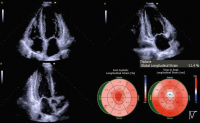

Abbildung 1: Echokardiographie bei Erstvorstellung

Abbildung 2: Echokardiographie bei erneuter Vorstellung: reduzierter globaler longitudinaler Strain (GLS; -11 %) mit „relative apical sparing“-Muster